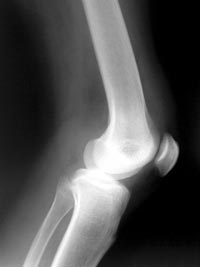

典型的慢性膝盖损伤是膝盖骨肌腱炎。这是指髌骨肌腱承受了太多的压力。这是最常见的体育运动,有很多跑或跳。当压力过大时,肌腱就会发炎和疼痛。如果它变得非常糟糕,它甚至可能开始退化。